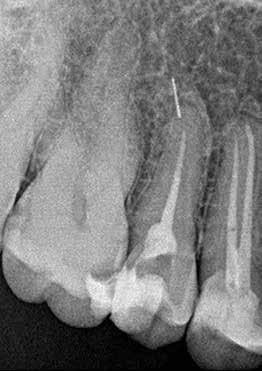

Hölgy páciensem az első konzultáció során tipikus kórtörténetet vázolt fel: Gyermekkora óta szeretett volna fogszabályozó készüléket, hiszen mindig is zavarta a class 2-es eltérésnél tipikusan jellemző nagy overjet (1-3. képek), és természetesen az ezáltal kifelé álló felső metszőfogai, részben a felső metszők protrúziója, részben pedig a disztálisan elhelyezkedő mandibula miatt. Annak ellenére, hogy több fogszabályozó szakorvosnál is járt az évek során, de mivel saggitális eltérése és az alsó metszőfogak torlódása miatt négy kisőrlőfog extrakcióját, illetve emellett sokszor állcsont műtétet is javasoltak neki, nem vágott bele a kezelésbe (4-5. képek).

A fogorvosa – nagyon helyesen – felhívta a figyelmét, hogy parodontális státusza is valószínűsíthetően romlani fog az eltérése miatt, újabb kört futott, immár 39 évesen, de még mindig premoláris fogak húzása és állcsontműtét nélkül szerette volna a fogszabályozást.